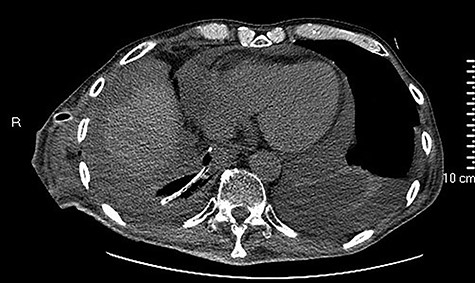

Initial CT showing a right hydropneumothorax after chest tube placement.

We present the clinical case of a 65 years old male patient submitted to totally minimally invasive Ivor Lewis esophagectomy after neoadjuvant chemo-radiotherapy for esophago-gastric junction adenocarcinoma (ypT2N0M0). A month after the surgery, the patient referred to our Emergency Department complaining acute dysphagia and asthenia. He presented with hypotension and tachycardia; laboratory blood tests revealed a

high PCR (291 mg/L) and the CT scan showed a right hydropneumothorax (Fig. 1). The first suspicion was an anastomotic leak and, in consideration of the hemodynamic instability and the severe septic state, the patient was submitted to emergency surgery. We performed a thoracoscopy with intraoperatively esophagogastroduodenoscopy which revealed a perforated prepyloric ulcer of the gastric tube. We therefore proceeded with accurate pleural toilette and closed the perforation with surgical stiches. At the end of the procedure, two thoracic drains and a naso-gastric tube with the distal end near the suture were placed. An additional naso-duodenum enteral feeding tube to ensure adequate nutrition was positioned. The patient was admitted in the Intensive Care Unit and supported with inotropic drugs, broad-spectrum antibiotics and proton pump inhibitor therapy. In the following days, the patient’s conditions improved allowing his extubation and his transfer to the surgical ward. Unfortunately, imaging and endoscopic check revealed a recurrent perforation. Considering the failure of the conservative approach, we decided to start the E-VAC Therapy on his 21st post-operative day (POD), using the Eso-SPONGE® System (B. Braun Surgical, S.A. Carretera De Terrassa, Rubi, Spain), firstly placed intraluminal because of the reduced size of the wall defect (Fig. 2). After three E-VAC replacements we did not observe any endoscopic or radiologic improvements. Moreover, on his 35th POD, due to a new impairment of vital signs, the patient underwent a second surgical treatment, with a new pleural toileting and another unsuccessful attempt of closing the conduit defect surgically. Considering the prolonged hospital stay, we placed a feeding jejunostomy. We proceeded with a new attempt of E-VAC, this time by placing it intracavitary (Fig. 3 and Fig. 4). The E-VAC was changed every 48–72 hours, reshaping the dimension of the sponge every time according to the size of the cavity. We observed a progressive reduction of the cavity size during the seriated endoscopic and CT evaluation. Considering the continuous improvement of patient’s clinical condition we discharged him after 84 days of hospitalization, with the E-VAC in place. The device replacement was carried on twice a week as an outpatient treatment, until its definitive removal (Fig. 5). The total duration of the therapy was 37 days with 13 E-VAC intracavitary interventions. Seven days after the device removal we performed an upper gastrointestinal X-Ray with oral contrast that showed no contrast medium leakage. The patient was therefore allowed to resume oral intake. At 6 months follow up the patient was in good clinical conditions; radiological test and endoscopy showed no abnormalities.